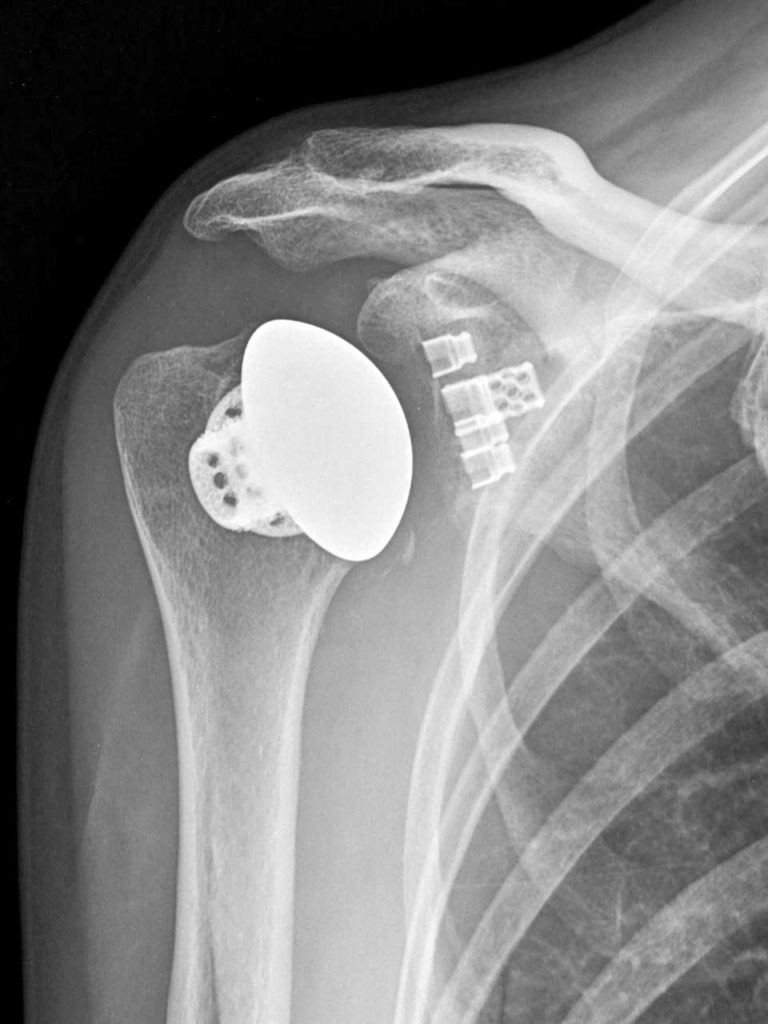

Voici la radiographie post-opératoire montrant l’épaule sans tige et la glène de la cage d’équinoxe, imprimées au laser. Image fournie par le Dr. Stephanie Muh.

« L’une des caractéristiques que je préfère de l’implant Stemless est sa structure de cage osseuse qui est conçue pour fournir une fixation initiale par pression tout en permettant une croissance osseuse. Cet élément de conception intentionnel, ainsi que la structure poreuse conçue pour imiter la nature trabéculaire de l’os spongieux, le différencie de ses concurrents », a déclaré le Dr Muh.